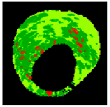

Since clustering algorithms will not return the same cluster index value every time, the colour of each cluster should be determined. With respect to the colour of each cluster, its matching plaque components can be determined as NC: red, DC: white, FI: dark green, and FF: light green [45].

The result of the clustering algorithms will be strongly affected by the presence of outliers that do not belong to any of the clusters [28]. The purpose of outlier detection is to find small groups of pixels that are not similar to the rest of the pixels belonging to the same cluster [72]. Figure 5 illustrates the outliers with dark green, light green, etc., in an NC image. The zoomed area (b) is indicated by the blue box in the original image (a).

Figure 5.

Outliers in an NC image: (a) original image, and (b) zoomed area.

To provide more reliable results, outliers should be removed from the generated clusters. NC and DC images play an important role in TCFA detection; therefore, their outliers are removed for modifying the training set. First, the Euclidian distance between pixels belonging to the NC and its centre are calculated. Then, for each pixel in the NC image, if its distance is greater than the defined threshold value (TNC), then this pixel is an outlier, and its intensity should be replaced with zero. Based on the sub experiments, the value of TNC is changed, and intra-cluster distance (the distance between pixels and the centroid within a cluster) for the NC image are calculated. The value of TNC = 200 gave the best result for the minimum distance between pixels of the NC and its centre. In addition, outliers of DC image are removed in the similar way [45].